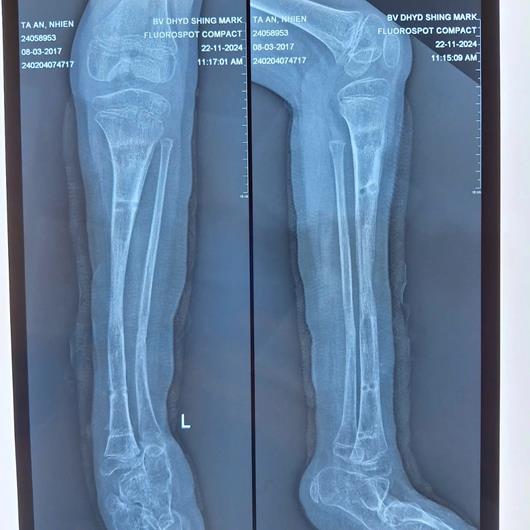

Theo GS-TS-BS René D.esser, kỹ thuật kéo dài chi đòi hỏi phải được thực hiện bởi bác sĩ tay nghề cao, nhiều kinh nghiệm. Đến nay, qua phim chụp X-Quang nhận thấy xương chân bé gái đã lành, các bác sĩ tiến hành tháo khung cố định ngoài, bé đang tiếp tục được tập vật lý trị liệu, tập đi để trở về cuộc sống bình thường.

Hình ảnh đôi chân của bé gái trên phim chụp X-Quang sau khi được phẫu thuật kéo chân trái.